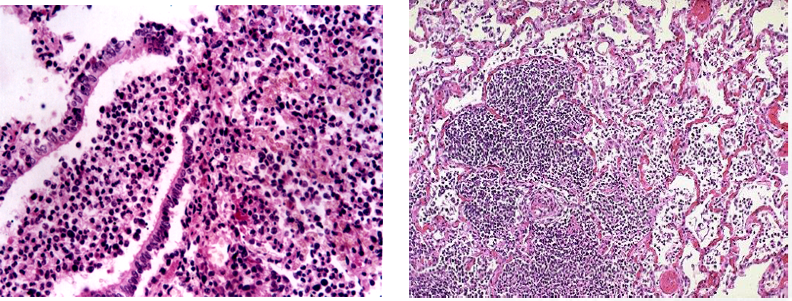

病毒性肺炎的基本病变为急性间质性肺炎,但病变形态常多样化,常由多种病毒混合感染或继发细菌感染所致。

图2-1

(2)严重的病例病变可波及肺泡腔,肺泡腔内可见多少不等的浆液、纤维素,单核细胞、巨噬细胞等。支气管、肺泡壁组织发生变性坏死。渗出明显者,浆液纤维素性渗出物浓缩在肺泡腔面形成一层均匀红染的膜状物,即透明膜。

图2-2 肺泡腔内渗出物

图2-2 透明膜

(3)在麻疹肺炎时,增生的支气管粘膜上皮和肺泡上皮细胞常形成多核巨细胞(巨细胞肺炎)。病毒性肺炎病理诊断的重要依据是找到病毒包涵体。病毒包涵体常呈圆形、椭圆形,红细胞大小,嗜酸性红染,周围有一清晰的透明晕。病毒包涵体可见于上皮细胞核内(如腺病毒)、胞浆内(如呼吸道合胞病毒)或胞核、胞浆内均有(如麻疹病毒)。病毒性肺炎若合并细菌感染,常伴化脓性病变,从而掩盖病毒性肺炎的特征。